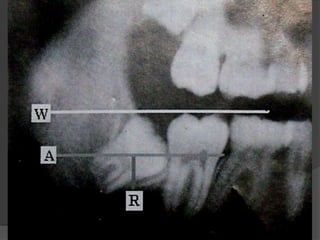

Winters “WAR” lines

 White line: Line joining the occlusal surfaces/heighest

cusps tips of all erupted molars, extending up to the

ramus. It indicates the difference in occlusal level of

second and third molars.

 Amber line: Represents the bone level distal to the 3rd

molar, extended anteriorly along the crest of interdental

septum. This line denotes the alveolar bone covering

the impacted tooth and the portion of the tooth not

covered.

 Red Line: Drawn perpendicular from Amber line to the

imaginary point of application of elevator on the 3rd

molar. It indicates the amount that will have to be

removed before elevation i.e. the depth of the tooth in

bone and the difficulty encountered in removing the

tooth